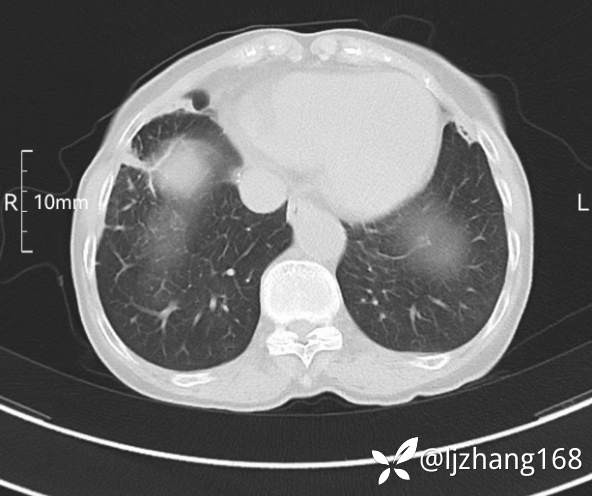

74岁女患,反复咳嗽2月,右肺空洞性病变,炎症OR肿瘤(有病理)

简要病史:2月前开始受凉后出现咳嗽,咳少许白色粘液痰,痰不易咳出,无痰中带血及咯血,无畏寒发热,外院胸部CT提示右下肺空洞病变,脓肿可能性大,常规抗感染治疗效果不佳。既往否认“糖尿病”等病史,有高血压基础病史,无吸烟史。

辅助检查:胸部CT右肺下叶前基底段结节并空洞

临床诊断:右肺空洞:脓肿?